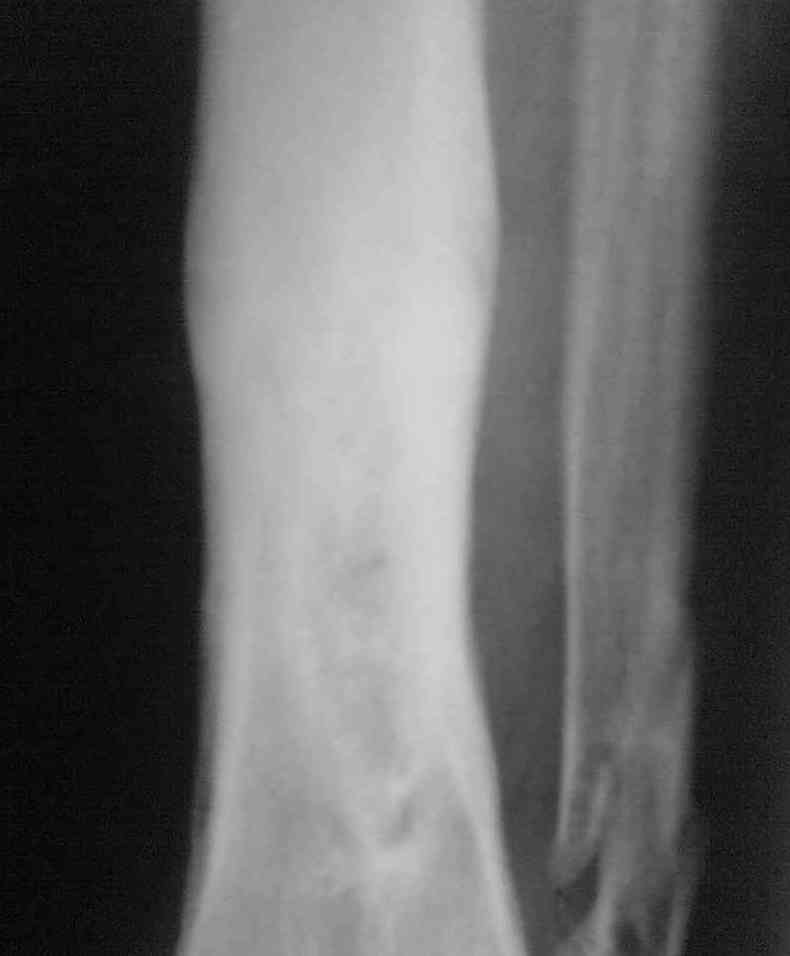

Здравствуйте коллеги! Прошу помочь с лечением больного. Мужчина в полном расцвете сил в апреле 2004 года получил травму - открытый оскольчатый перелом голени. Через 2 дня произведён МОС большеберцовой кости пластиной АО и винтами. Послеоперационный период осложнился остеомиелитом. Через 3.5 месяца пластина удалена. В марте 2005 года оперативное лечение в г. Екатеринбурге - санирование очага, некрэктомия. В июне 2006 года в ОКБ произведена секвестрэктомия, через неделю некрэктомия. Неоднократно получал антибактериальную терапию, в результате чего сформировалась сенсибилизация ко многим антибактериальным препаратам. В данный получает перевязки. Локально сохраняется кратерообразная гнойная рана, размерами до 4 х 3 см. Хотелось бы узнать Ваши мнения по поводу дальнейшего ведения данного пациента.

Выкладываю снимки в хронологическом порядке. Снмки все какие есть у больного.

Количество не заменяет качества, поэтому не стоит выкладывать весь хлам, какой удастся найти у пациента. Лучше сделать 1)свежие 2)хорошего качества рентгенограммы, чтобы оценивать ситуацию по ним, а не по мутным огрызкам.